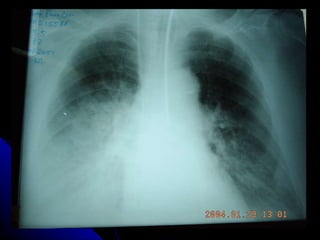

RADIOLOGIA Los infiltrados pueden ser muy pequeños y difíciles de apreciar especialmente en radiografías portátiles. La pausa inspiratoria es prácticamente imposible cuando el paciente se encuentra en ventilación mecánica haciéndolas menos específicas para el diagnóstico. La Tomografía Axial del tórax puede diagnosticar hasta en un 26% más, infiltrados pulmonares a más de definirlos más exactamente que la placa simple del tórax

RADIOLOGIA Los infiltradospueden ser muy pequeños y difíciles de apreciar especialmente en radiografías portátiles. La pausa inspiratoria es prácticamente imposible cuando el paciente se encuentra en ventilación mecánica haciéndolas menos específicas para el diagnóstico. La Tomografía Axial del tórax puede diagnosticar hasta en un 26% más, infiltrados pulmonares a más de definirlos más exactamente que la placa simple del tórax